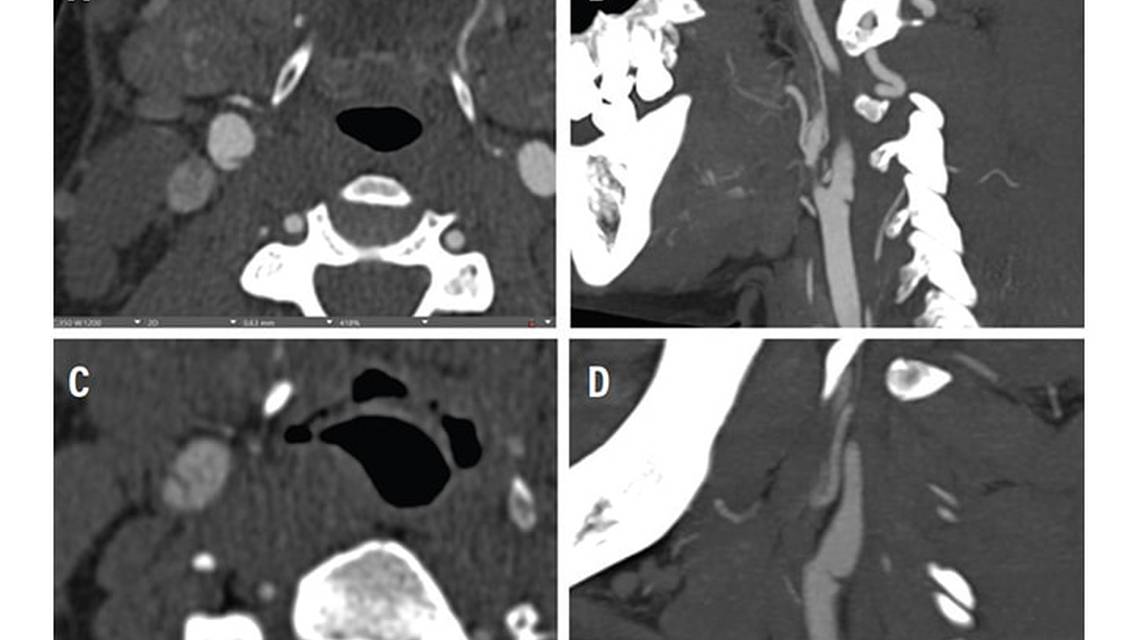

CAWs present as nonatheromatous, shelf-like projections affecting the posterolateral wall of the cervical internal carotid artery (Figure 1).4 The pathophysiology of CAWs was first described in 1968 as a cause of recurrent left hemispheric ischemia in an otherwise healthy young individual.5 Subsequent cases were described using different monikers, including “atypical fibromuscular dysplasia”, “septa”, and “diaphragms”,6 with the term “carotid artery web” increasing in prevalence since around 2014.

CT angiography (CTA) is a preferred method of CAW detection because of its noninvasive nature and detailed imaging. CAWs appear on CTA as thin defects along the posterior side of the carotid bulb, showing up as septa or filling defects on scans.1 CTA delivers high-resolution images quickly, but is not as definitive as DSA, and involves the use of ionizing radiation and iodine-based contrast.